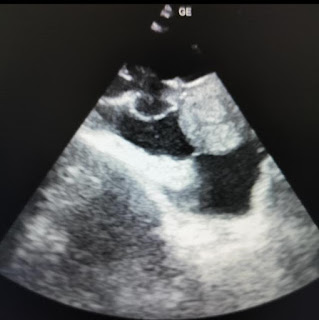

His cardiac echo on day 1 is available here πŸ‘‡

It shows anteroseptal and infero septal dyskinesia.

RB: Given the dyskinetic segment, with albeit good lvpw contractility the overall visual EF in the above video appears to be 30%